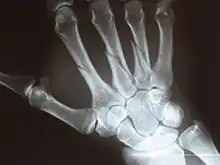

X-ray

X-ray image of human infant left hand.